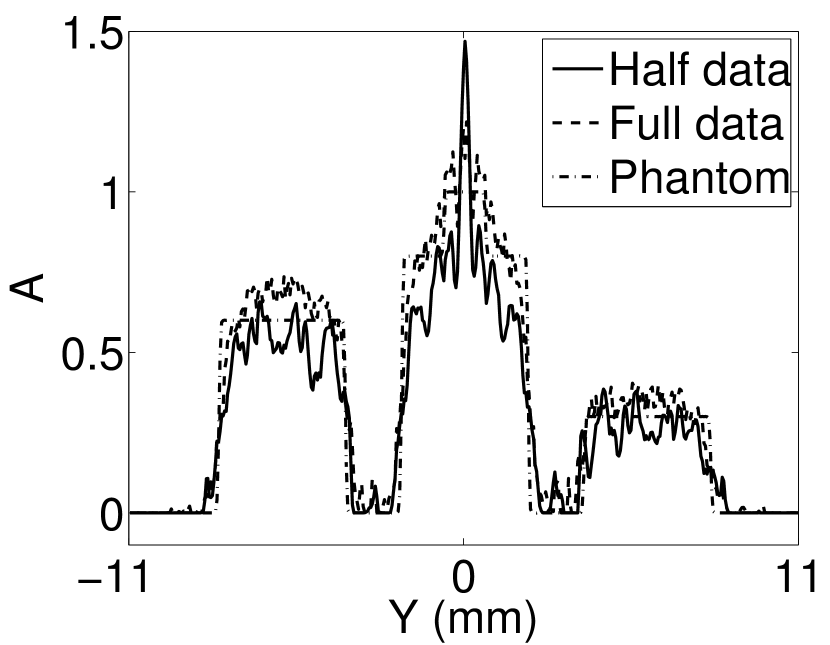

V-A3 Effect of data incompleteness

Incomplete, or sparsely sampled, data sets are sometimes acquired in practice. To study the effect of data incompleteness on the VP algorithm, we reconstructed images from data corresponding to half of the equally spaced transducers (). Because the data were noiseless, no explicit regularization was employed () in the conventional reconstruction algorithm. However, the explicit regularization was still employed in the VP algorithm because of the ill-posed nature of the joint reconstruction problem. The results are shown in Figure 5. As expected, use of the incomplete data set resulted in less accurate reconstructed images for both the conventional iterative reconstruction method and the VP algorithm. However, this effect was more pronounced for the VP algorithm. Note that for the VP algorithm, larger values of the regularization parameters were applied when the incomplete data set was employed than when the complete data set was employed (Figure 5(h) and 5(g)).